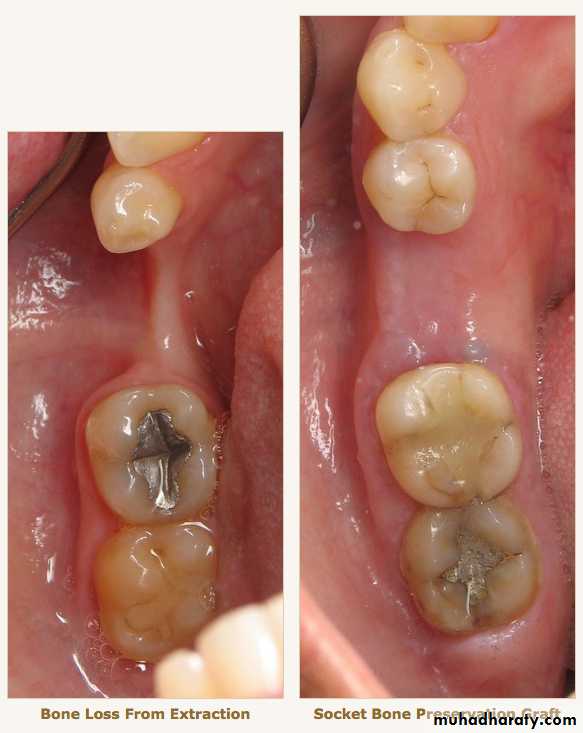

Radiographic examination:• Cyst

• Tumor• Retained root

• Periodontal condtion of remaining teeth

• Bone fracture

• Extend of bone resorbtion

• Locate cannal

• pt. education